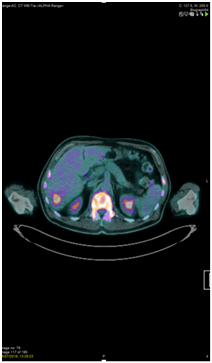

A whole-body PET-CT scan was performed. This revealed FDG avidity on the left side of the neck with further abnormal foci noted within the left tonsillar bed, lateral left side of the tongue base and lower cervical node chain (Figure 2). It also showed tracer uptake of the skull vault, skull base, mandible, all of the vertebral bodies, both humeri, both scapulae, multiple ribs, sternum, pelvis and both proximal femora. At these sites there was evidence of mixed lytic and sclerotic disease. No encroachment of the spinal cord was seen. Three small FDG avid intrahepatic lesions were also noted and there was a small FDG avid lower right-sided para-aortic node also (Figure 3). Spleen, kidneys, adrenals, bowel and prostate were noted to be normal. Laboratory panel showed a haemoglobin of 81g/dL, white cell count of 7.2, platelets of 5 and an LDH of 1057. Other markers, including calcium, were within the normal range. A blood film showed a leucoerythroblastic picture with normocytic, normochromic red cells, some polychromatic cells, thrombocytopaenia, a left neutrophil shift, myelocytes and occasional blast cells. Lymphocytes were small and mature.

Figure 3 18FDG PET confirming liver and vertebral mets.